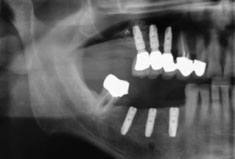

DVT mit 3D-Planung